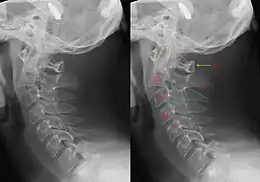

On the day of the execution, the practice was for Pierrepoint, his assistant and two prison officers to enter the condemned man's cell at 8:00 am. Pierrepoint secured the man's arms behind his back with a leather strap, and all five walked through a second door, which led to the execution chamber. The prisoner was walked to a marked spot on the trapdoor whereupon Pierrepoint placed a white hood over the prisoner's head and a noose around his neck. The metal eye through which the rope was looped was placed under the left jawbone which, when the prisoner dropped, forced the head back and broke the spine. Pierrepoint pushed a large lever, releasing the trapdoor. From entering the condemned man's cell to opening the trapdoor took him a maximum of 12 seconds. The neck was broken in almost exactly the same position in each hanging—the hangman's fracture.[33][34]

- ↑ If the drop was too short, the condemned man was liable to be strangled to death; too long and there was a risk of decapitation. If the drop was calculated correctly, the prisoner's neck should be broken, resulting in a quick death.[30]